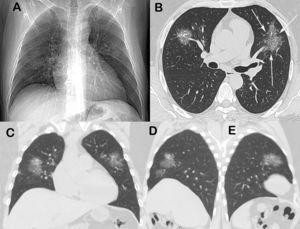

koronavirusos tudogyulladas rontgen

Koronavírusos tüdőgyulladás röntgenfelvétele (a fehér rész az érintett)

Forrás: egeszsegkalauz.hu